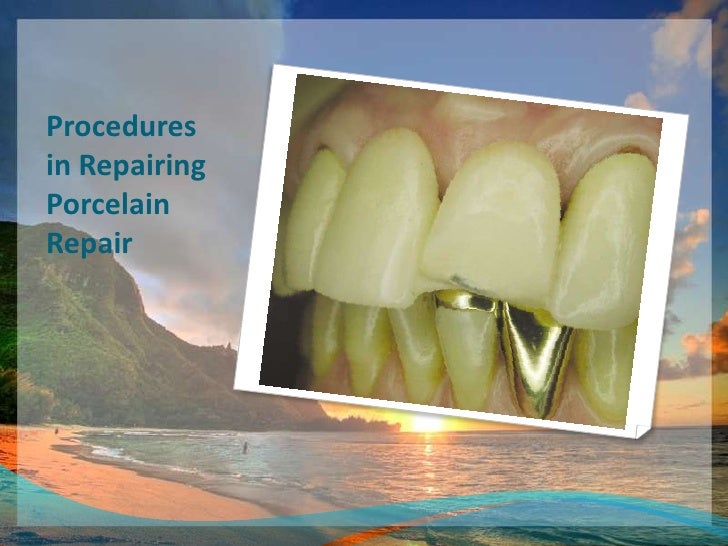

A Technique For Repair Of A Fractured Porcelain-Fused-to-Metal Bridge

www.dentistrytoday.com

www.dentistrytoday.com

Repairing Fractured Pfm | PPT

www.slideshare.net

www.slideshare.net

Repairing Fractured Pfm

www.slideshare.net

www.slideshare.net

Repairing Fractured Pfm

www.slideshare.net

www.slideshare.net

Repairing Fractured Pfm

www.slideshare.net

www.slideshare.net

Repairing Fractured Pfm

www.slideshare.net

www.slideshare.net

Repairing Fractured Pfm

www.slideshare.net

www.slideshare.net

A Technique For Repair Of A Fractured Porcelain-Fused-to-Metal Bridge

www.dentistrytoday.com

www.dentistrytoday.com